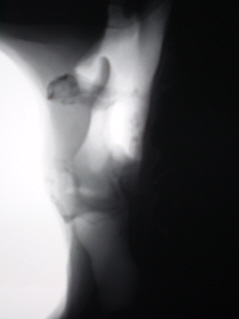

Рентгенологическое исследование гортани - томография проведено по стандартной методике (на РДК на 3 рабочих места – «Вироматик».

На томограммах гортани (иллюстрации 3, 4) определяется деформация гортани, с резким утолщением её стенки слева, выражена асимметрия надсвязочного и связочного пространств, с выраженной нечёткостью и деформацией контура стенки надсвязочного пространства слева.

3.